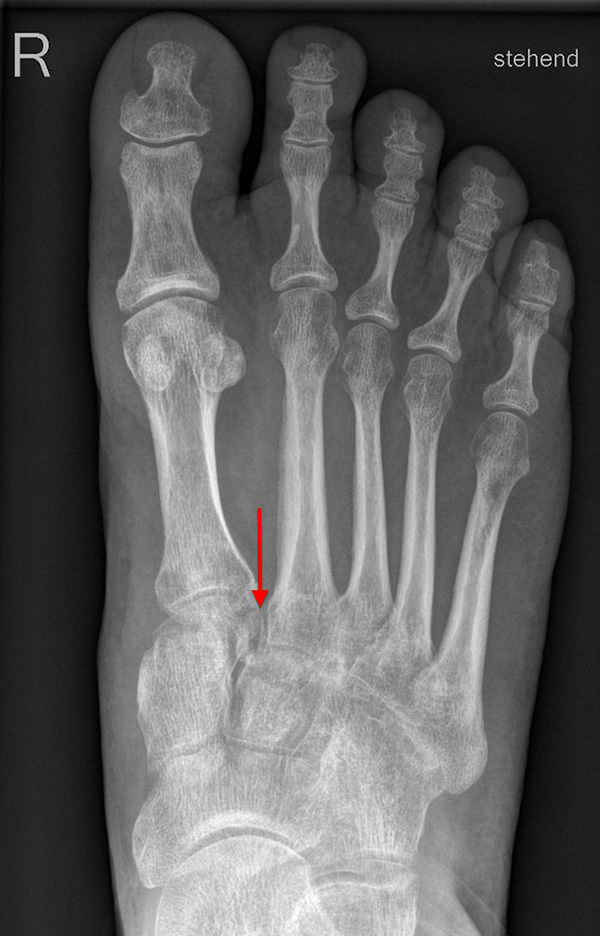

Standardisierte Röntgenaufnahmen des betroffenen Fußes, dorsoplantar (dp), streng seitlich sowie eine Schrägaufnahme werden angefertigt. Diese sollten möglichst unter Belastung angefertigt werden, da in den unbelasteten Aufnahmen insbesondere diskrete Veränderungen häufig nicht sicher zu erkennen sind.

Auf den dp-Aufnahmen sollte der mediale Rand der Metatarsale-2-Basis mit dem medialen Rand des Os cuneiforme intermedium eine homogene Linie ohne Stufenbildung bilden (Abb. 7+8). Außerdem ist auf den Abstand zwischen der Metatarsale-1- und -2-Basis zu achten. Dieser sollte nicht größer als 2 mm bzw. im Vergleich zur Gegenseite nicht mehr als 1 mm erweitert sein. In bis zu 90% der Fälle zeigt sich ein sogenanntes „Fleck sign“ (Abb. 9), ein knöchernes Fragment zwischen der Metararsale-1- und -2-Basis im Sinne eines knöchernen Ausrisses des Lisfranc-Ligaments an der Metatarsale-2-Basis 211936410. Oft liegen zusätzliche Frakturen der Metatarsalebasen oder der Tarsale vor, die ebenfalls identifiziert werden sollten. Bei jeder Mittelfußbasisfraktur sollte umgekehrt an eine Lisfranc-Verletzung gedacht werden.

Zum Lesen der Bildbeschreibung und zur Vollansicht bitte die Bilder anklicken.

In der Schrägaufnahme sollte der mediale Rand des Cuboids mit dem medialen Rand der Metatarsale-4-Basis eine homogene Linie bilden.

In der seitlichen Aufnahme ist auf Dislokationen und Subluxationen in den Tarsometatarsalgelenken sowie auf einen Verlust des Fußlängsgewölbes zu achten. Bei Instabilitäten des 1. Strahls bzw. Abflachung des Fußlängsgewölbes tritt in der Seitaufnahme die plantare Kontur des Os cuneiforme mediale tiefer im Vergleich zur Basis des Metatarsale 5. Darüber hinaus sollte die Cyma-Linie im Bereich des Chopartgelenkes in der Seitaufnahme eine harmonische S-förmige Linie bilden.

Insbesondere bei rein ligamentären, aber auch subtilen Verletzungen können belastete Vergleichsaufnahmen der unverletzten Gegenseite oder Streßaufnahmen des verletzten Fußes unter Bildwandlerkontrolle hilfreich sein 161129584 (Richter 2007).

Aber auch in den belasteten Röntgenaufnahmen sind subtile Frakturen und Luxationen oder rein ligamentäre Verletzungen oft nicht sicher darstellbar 7.